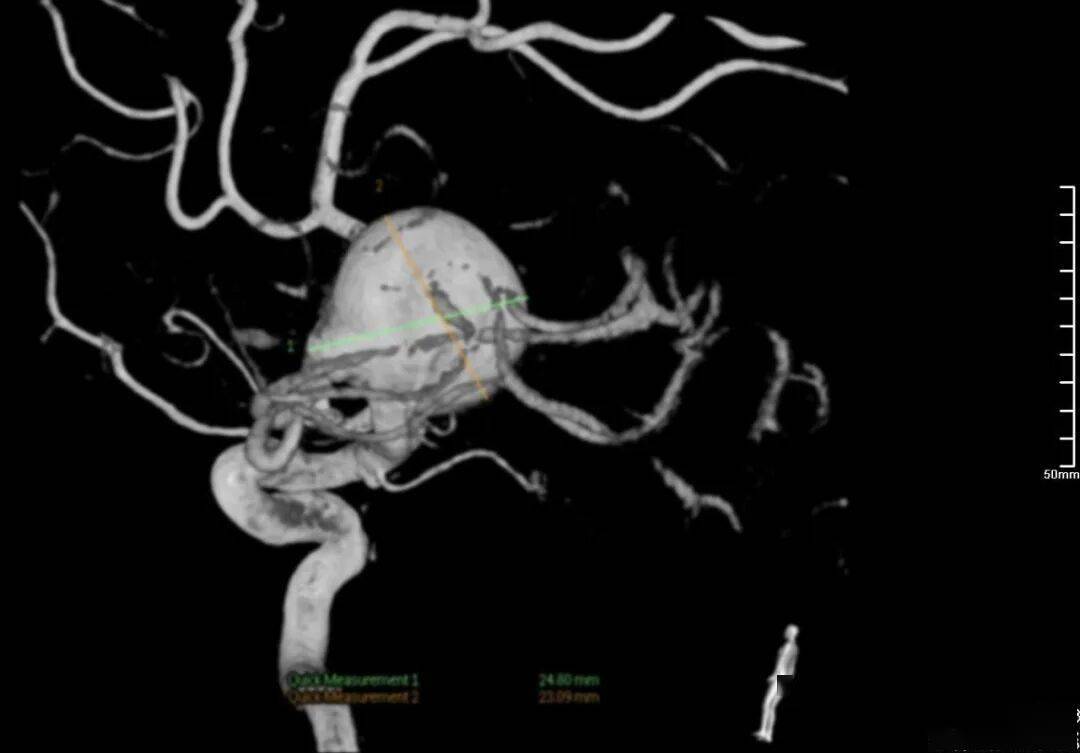

Lattice治疗左侧大脑中动脉M1段巨大型动脉瘤

术前影像

术前正位DSA

术前侧位DSA

术前核磁

初步诊断:左侧大脑中动脉M1段动脉瘤

侧别、位置:左侧

动脉瘤的形态:囊性

动脉瘤大小:长24.8mm、宽23.1mm、高20mm

动脉瘤颈宽度:6.2mm

载瘤动脉直径:远端3.1mm,近端3.9mm

治疗方案:Lattice血流导向密网支架置入术+弹簧圈辅助栓塞